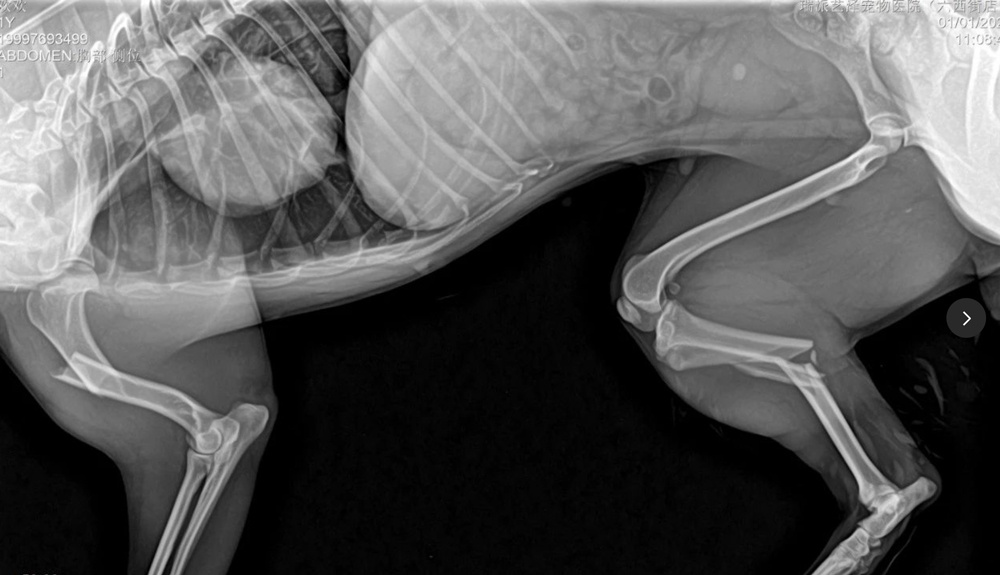

我在獸醫工作中看過不少三肢骨折、兩肢骨折的病例。對於多肢骨折的病例,在規劃手術時考慮機械力學的穩定性非常重要。術後動物行走時需要用該腿負重,如果機械穩定性較差,術後負重容易導致植入物斷裂、固定失敗。設計合理的植入物固定方案,在確保機械穩定性的同時,也要考慮骨折的生物特性,確保在植入物疲勞發生前快速癒合。手術中充分保護軟組織至關重要,僅僅追求植入物的穩定性而損傷過多軟組織影響癒合是不夠的。

動物基本資料:鄉村犬,7公斤1歲,骨折原因:車禍

右脛骨幹粉碎性骨折(閉合性)